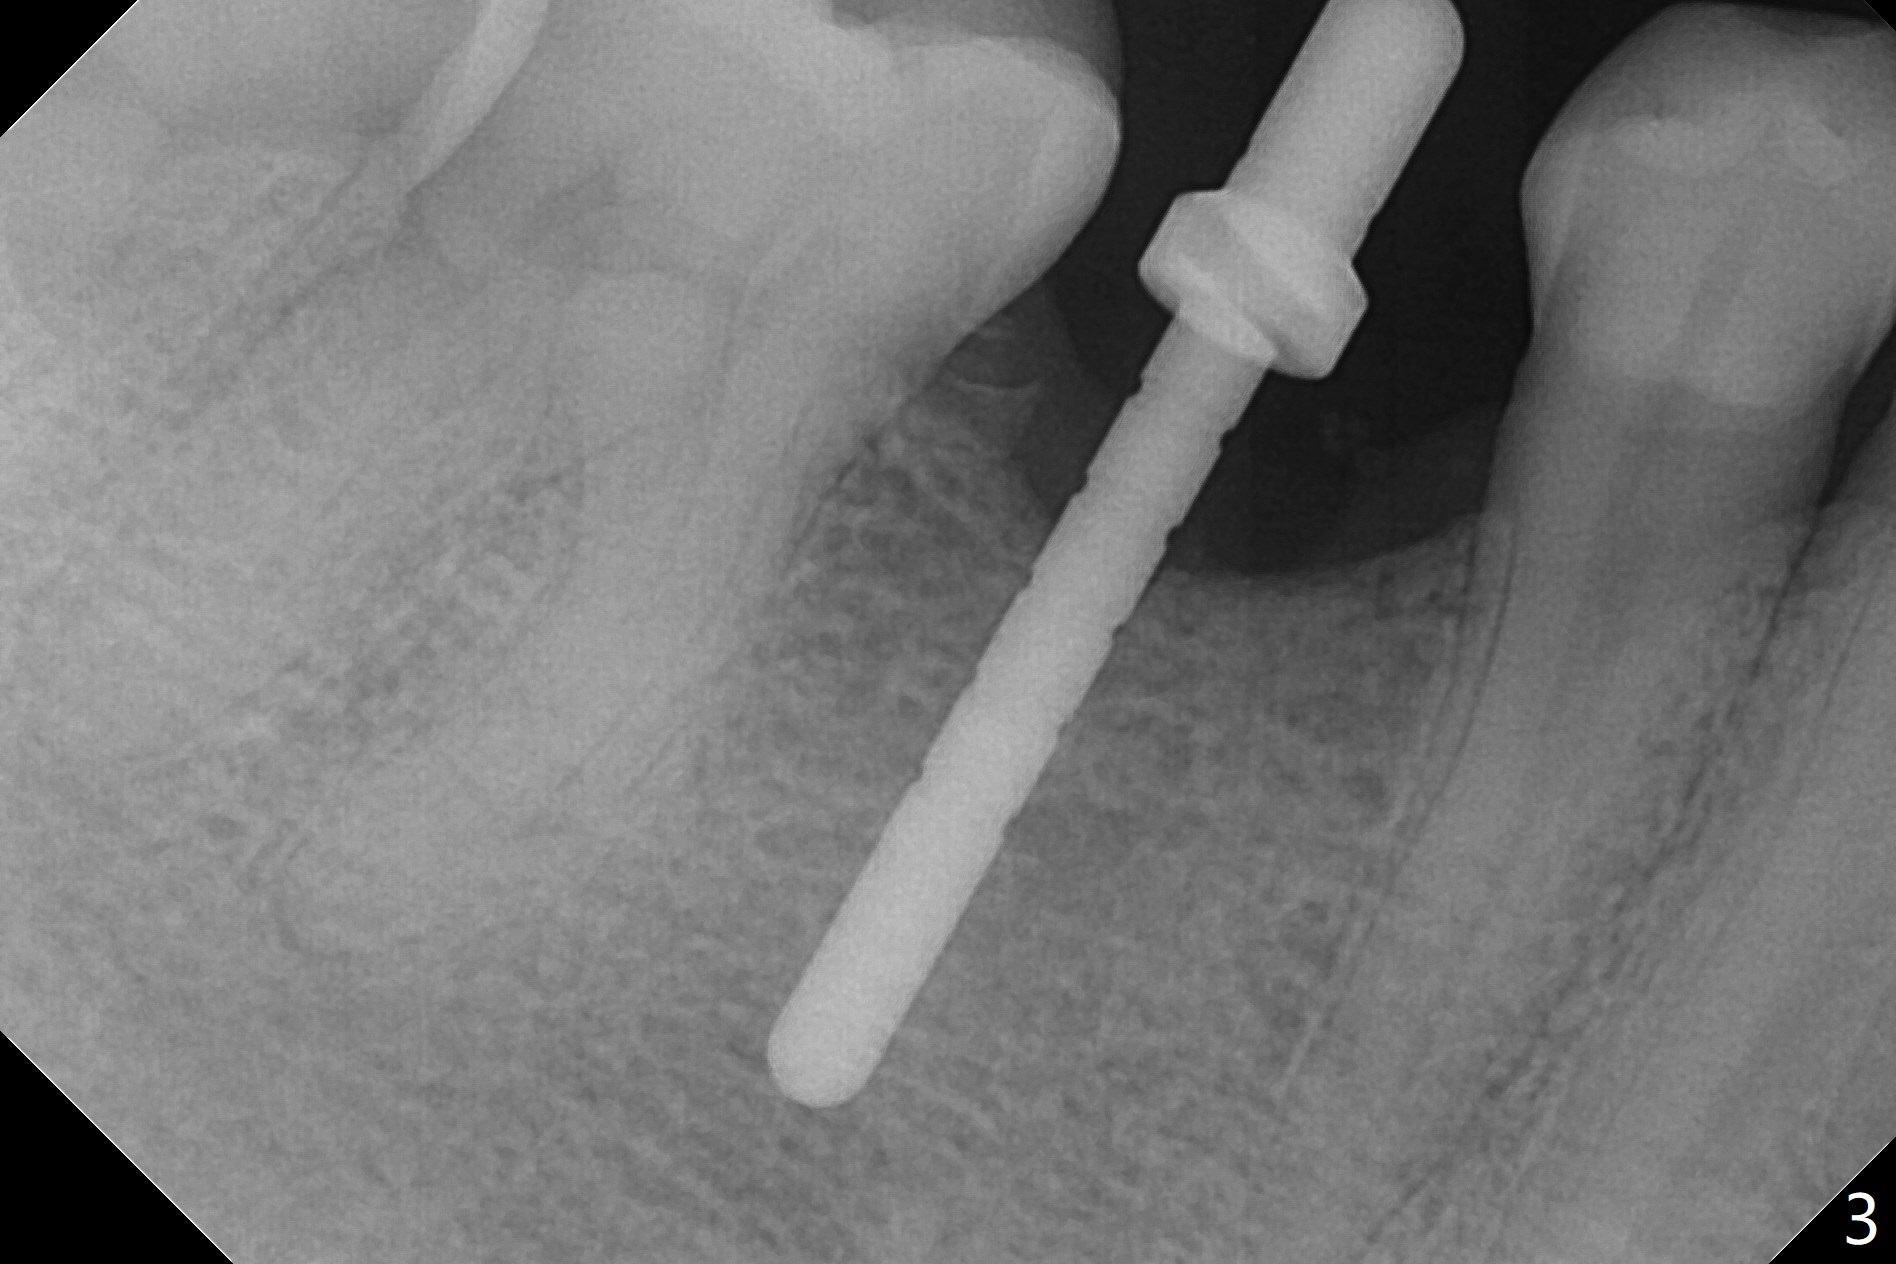

The base of the edentulous ridge at #29 looks wide (Fig.1), but the most coronal portion is the thin soft tissue (Fig.2). It appears that there has been bone resorption since extraction. The initial osteotomy depth is 11.5 mm (Fig.3). Since the Mental Loop seems to be nearby, the depth of subsequent osteotomy (3 mm) remains the same (Fig.4). Although the final depth of osteotomy is 13 mm, the implant placed is short (3.8x11.5 mm, Fig.5,6), as compared to the immediate implant (3.8x18 mm) at the contralateral side (#20). There is mild bone resorption mesially 4 months postop (Fig.7). The crown is loose (poor osteotomy position, guide necessity) 7 months post cementation immediately prior to 18 cementation, although there is no gross bone losss 1 year 7 months post cementation (Fig.8).